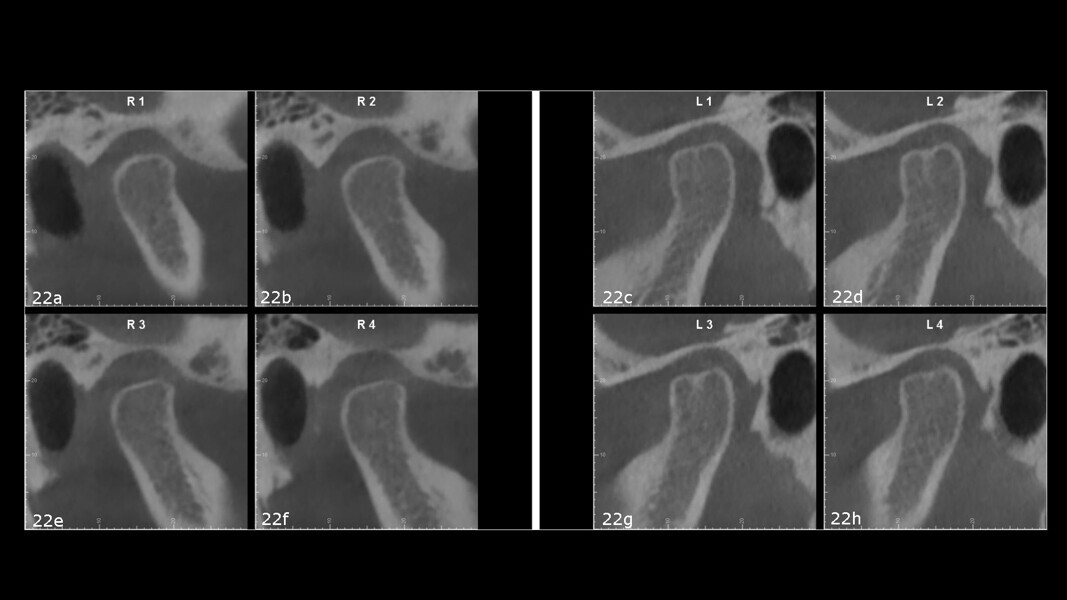

A virtual articulator mounting using MODJAW revealed a significant discrepancy between maximum intercuspation and centric occlusion (Fig. 21). CBCT imaging of the joints further confirmed joint pathology, showing inferior displacement of the right condyle, flattened articular surfaces on both condyles and a bifid morphology of the left condyle (Fig. 22). Given the presence of TMD symptoms, pronounced discrepancy between maximum intercuspation and centric occlusion, and clinical signs of gingival recession and abfraction lesions—all consistent with joint instability—we initiated therapy with a condylar repositioning appliance.